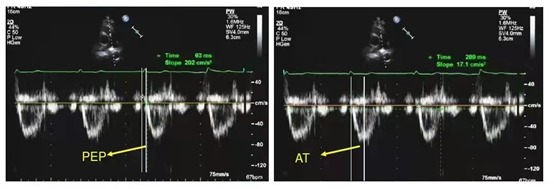

五、射血前期与加速时间比值PEP/AT法估测肺动脉收缩压

测量方法:右室射血前期(PEP):取胸骨旁大动脉短轴切面,PW取样容积放在肺动脉瓣上,记录肺动脉瓣收缩期血流频谱和心电图。

Q波起点至肺动脉收缩期血流频谱起点之间时间为PEP,正常值为77-115ms。

取肺动脉收缩期血流频谱起点至最高点的时间为肺动脉血流加速时间AT,正常值为137±24ms。

诊断标准:正常人PEP/AT<1 PEP/AT≥1即可诊断为肺高压。

肺动脉高压时右心收缩需要达到比乎时更高的压力方能使肺动脉瓣打开肺动脉瓣开放延迟,所以右室射血前期延长,同时,肺动脉压力增高,使得肺动脉瓣提前关闭,右室射血时间减少,PEP/AT>1。